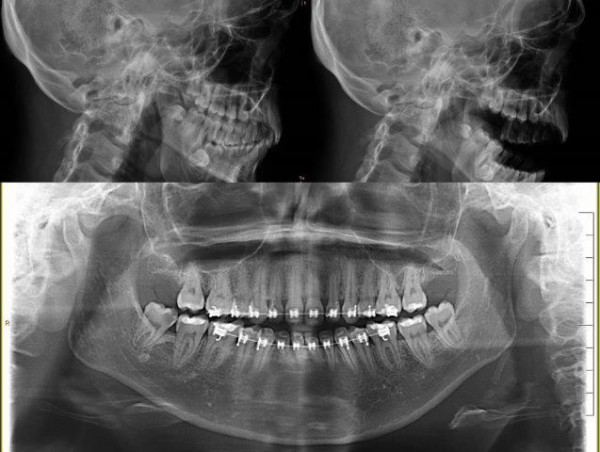

- Exposiciones teóricas por grupos de patologías con aplicabilidad práctica: cuando el caso lo requiera se realizará una demostración de cómo se puede solventar un problema: suturas, anestesia local, ferulización dental. Presentación de casos clínicos, que permitirán una mejor comprensión de los conceptos expuestos.Discusión.